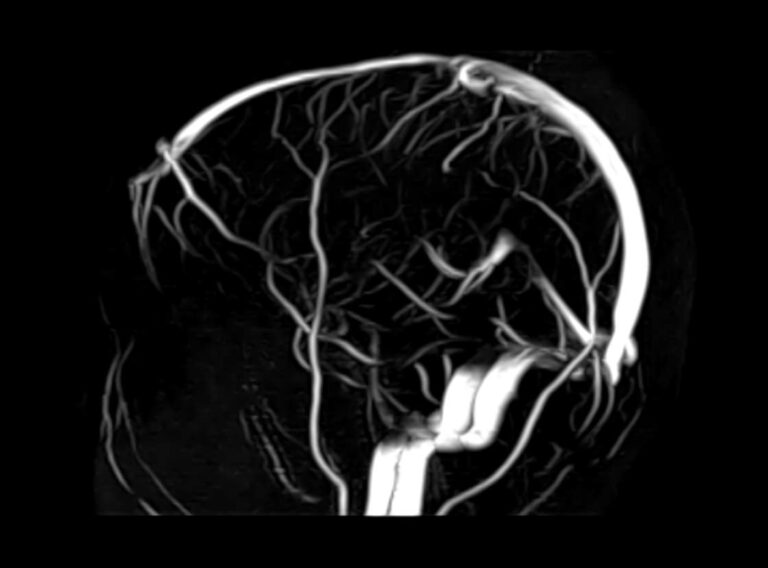

При помощи данного метода можно эффективно диагностировать следующие патологии и заболевания:

• сосудистые мальформации (аномальное сообщение между веной и артерией, смешивание венозной и артериальной крови);

• прорастание опухоли головного мозга в сосуд;

• тромбоз венозных синусов и вен;

• аномалии положения и развития вен;

• венозный застой;

• артерио-венозные мальформации — неправильное соединение сосудов врожденного характера;

• стенозы (сужение) сосудов.

МРТ вен мозга необходима перед хирургическими вмешательствами, для послеоперационного контроля и наблюдения за выявленным заболеванием в динамике.